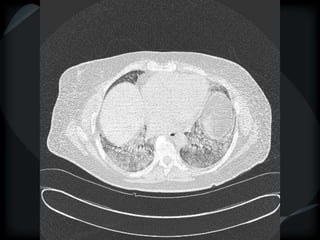

Airspace Patterns

 Perilobular pattern

COP – perilobular pattern